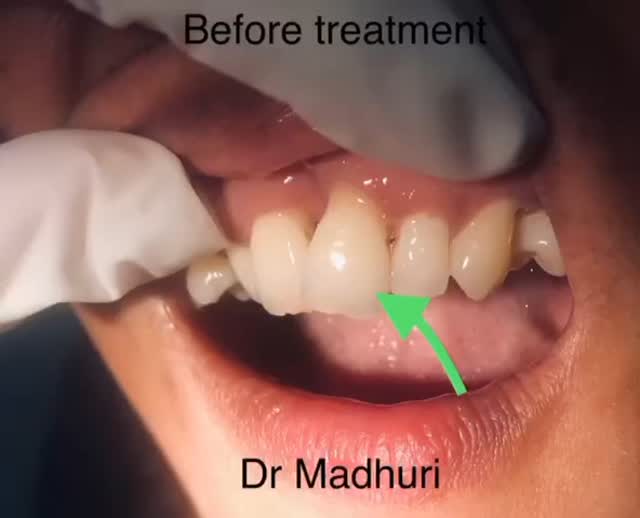

Explore Our Clinical Dental Gallery

Welcome to our official treatment gallery, showcasing the real results, smile transformations, and advanced dental care delivered by Dr. Madhuri. We believe that a picture is worth a thousand words when it comes to the art and precision of modern dentistry. Review our comprehensive visual portfolio below to see how our dedicated care helps patients achieve healthy, beautiful, and confident smiles.